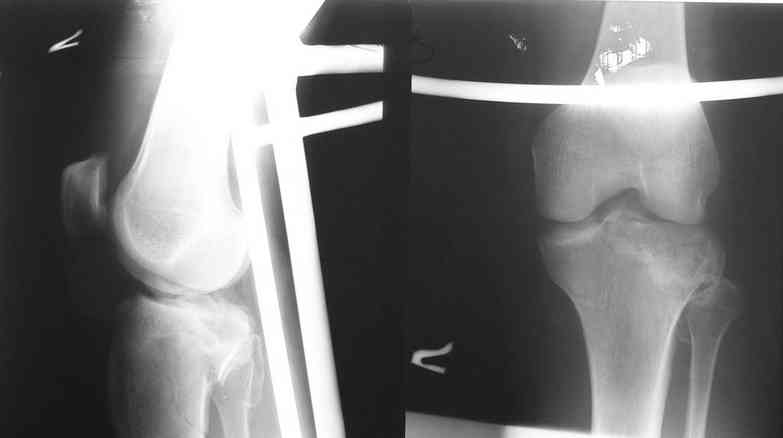

Уважаемый Леонид! Вы имеете дело с переломом Tibial plateau. Для того, чтобы можно было классифицировать перелом, представленных снимков КТ не достаточно, поэтому, если можно дайте снимки рентгеновские обыкновенные.

Скорее всего у Вашего пациента Бикондилярный перелом проксимальной тибии с депрессией латерального тибиального плато.

Такие переломы требуют анатомическую редукцию, насколько это возможности, поддерживающую фиксацию с помощью специальной платы для таких преломов, если она у Вас есть или аппаратом Илизарова, который наверняка у Вас есть.

Спасибо за ответ высылаю R- граммы пациента. Ранее как и в это раз оперировали открыто репонируя суставную поверхность из дополнительного окна по передней поверхности мыщелка дефект губчатой ткани заполняли аутотрансплантатом с гребня подвздошной кости или пористым никелид титаном и фиксировали мыщелковой пластиной. В данном случае межмыщелковое возвышение фиксировали проволочным швом окно для поднятия суставной поверхности сформировали по передне-наружной поверхности н/мыщелка, дефект заполнили аутокостью и фиксировали пластиной с угловой стабильностью с болтом-стяжкой. В ближайшие дни покажу контроль R-гр, КТ.